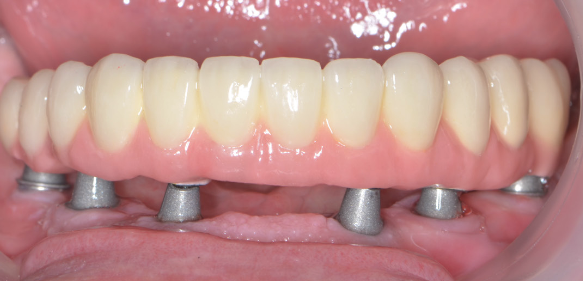

Pe baza scanărilor imagistice 3D (CBCT) se vor efectua măsurători ale înălțimii și lățimii osului mandibular, astfel încât medicul implantolog să poată decide dacă se pot insera implanturi direct sau este nevoie de adăugare de os în prealabil. Se realizează un ghid chirurgical care ajută la poziționarea precisă a implanturilor în os (Fig.3.6.4. dr. Ondine Lucaciu), iar în 24 de ore după această intervenție pacientul primește o punte provizorie fixă pe care o va purta un interval de 3-6 luni, perioadă necesară osteointegrării implanturilor, respectiv vindecării (Fig. 3.6.5). Această lucrare provizorie va fi înșurubată în 6 puncte, în cele 6 implanturi inserate în mandibulă (Fig. 3.6.6).

După acest interval lucrarea provizorie se îndepărtează, în fiecare implant se montează câte un dispozitiv necesar realizării amprentelor (Fig. 3.6.7) care vor servi tehnicianului dentar pentru realizarea punții definitive (Fig. 3.6.8 și Fig. 3.6.9). Realizarea acesteia se face în câteva zile, interval în care pacientul va continua să poarte lucrarea provizorie realizată inițial.

Lucrarea finală se va înșuruba pe componentele protetice ale implanturilor (Fig. 3.6.10 și 3.6.11), iar perforațiile de acces pentru șuruburi (Fig. 3.6.12) vor fi acoperite cu material compozit (Fig. 3.6.13). După fixarea definitivă (Fig. 3.6.14) puntea poate fi oricând detașată de către medicul dentist la nevoie, prin simpla îndepărtare a materialului compozit și desfiletarea șuruburilor de fixare.